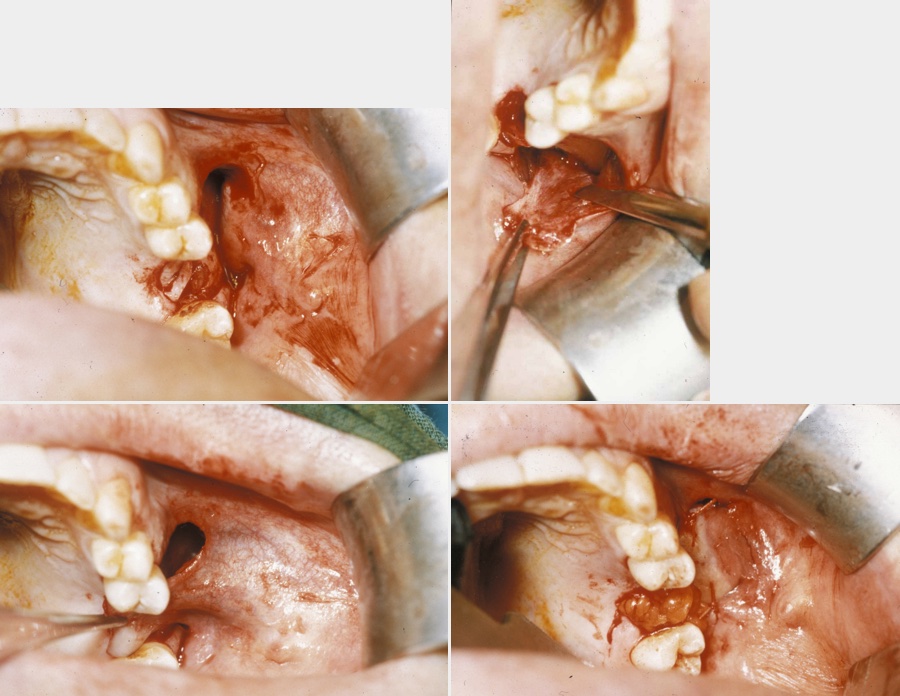

A combination of buccal fat pad and buccal advancement flap is probably the most effective way to close an oroantral fistula. The advantage of the technique is that the vascularised buccal fat pad fills the defect below the buccal advancement flap. This provides mucosal closure and thereby creates a double-layered vascularised closure that virtually has no chance of dehiscence and breakdown. The technique is illustrated in Figure 5.

Figure 5: Top left: combination approach using the buccal fat pad and the buccal advancement flap technique; top right: flap elevated; bottom left: flap mobilised; bottom right: fat pad inset, mucosa partially advanced.